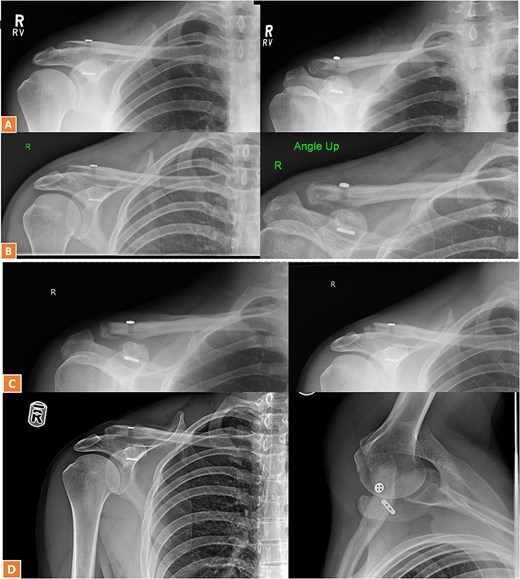

A 27-year-old male suffered a right lateral clavicle fracture after a fall (Fig. 5). He underwent TightRope fixation with stabilization of the coracoclavicular ligament. Rehabilitation was initiated early, and by three months, he had full shoulder motion and returned to overhead sports. Radiographs confirmed union, and the patient reported minor scar sensitivity and transient keloid formation, with no functional limitations (Fig. 6A–D).

Radiographs of third case showing a displaced lateral clavicle fracture with deformity.

(A, B) Radiographs showing healing of the third case and radiological union at 6 weeks and 3 months post-operatively. (C–D) Radiographs showing complete healing of the third case and union at 6 months and 12 months post-operatively.